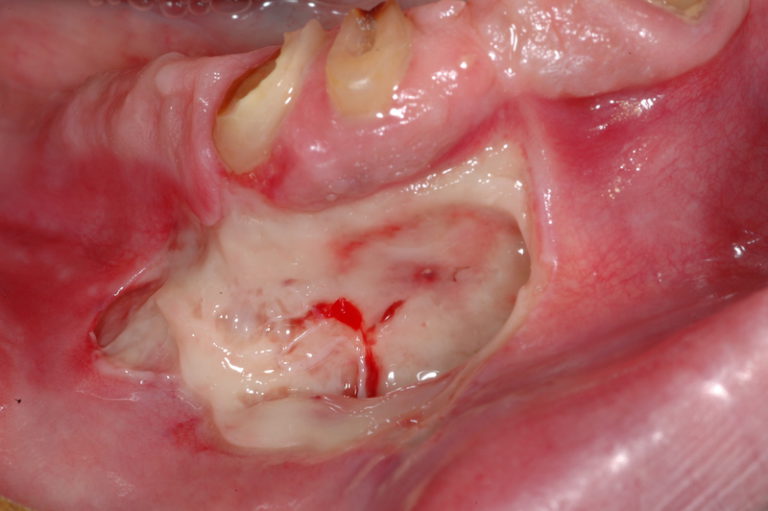

I bifosfonati rappresentano una classe di farmaci che agiscono bloccando il turnover del tessuto osseo. Somministrati per via endovenosa, vengono impiegati in oncologia per il